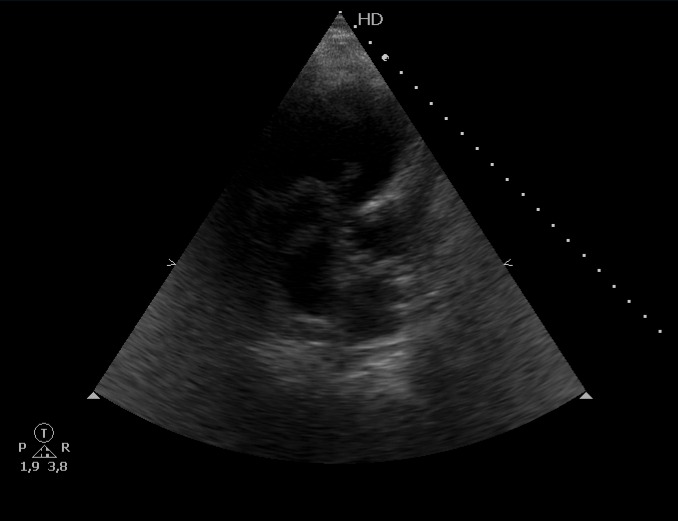

Escalas de riesgo probable para tromboembolismo pulmonar, cursando prueba de imagen que confirma patología y ampliando estudio con ecografía cardíaca que muestra presencia de émbolo intracardíaco.

Signos de disfunción del VD en el momento inicial, y mayor riesgo de muerte prematura.

Clasificación de trombo intracardíaco en Tipo A, B o C; el A tiene forma de gusano o serpiente, es móvil y suele asociarse a TVP.